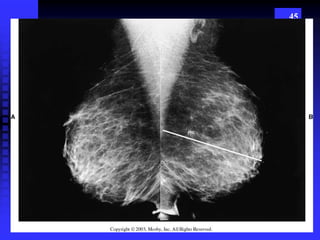

45